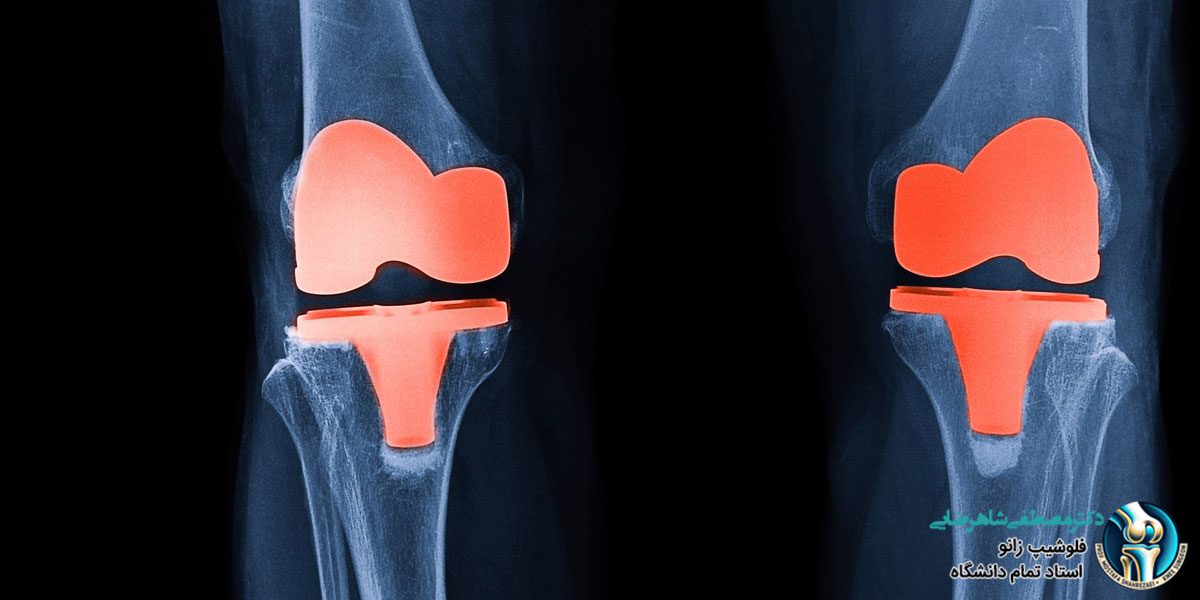

تعویض مفصل زانو یکی از شایع ترین جراحی های ارتوپدی است که برای بیماران مبتلا به آرتروز شدید، آسیب های زانو یا دیگر مشکلات جدی انجام می شود. با توجه به پیشرفت های اخیر در علم پزشکی و تکنولوژی های مورد استفاده در تولید پروتزها، نتایج این عمل جراحی بهبود یافته و پروتزهای زانو می توانند عمر طولانی داشته باشند. در این مقاله با دکتر مصطفی شاهرضایی متخصص ارتوپدی و زانو به بررسی عمر مفید پروتزهای زانو و مراحل فیزیوتراپی و ورزش های لازم برای بازتوانی پس از تعویض مفصل زانو می پردازیم.

عمر مفید پروتزهای زانو

پروتزهای زانو که در جراحی تعویض مفصل استفاده می شوند، معمولاً عمر طولانی دارند. بسیاری از مطالعات نشان می دهند که پروتزهای زانو می توانند ۱۵ تا ۲۰ سال عمر مفید داشته باشند و در بعضی موارد حتی بیشتر. عمر مفید پروتزهای زانو به عوامل مختلفی بستگی دارد، از جمله: